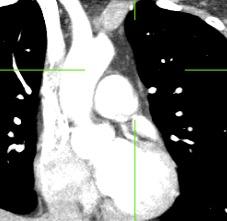

Diafragma “colgante” (“dangling sign”)

(“Dangling sign”)

TC. Mejor con multicorte. (reconstrucciones).

Diafragma discontinúo Herniación de la grasa omental

Desser TS et al.The dangling diaphragm sign: sensitivity and comparison with existing CT signs of blunt traumatic diaphragmatic rupture. Emerg Radiol 2010